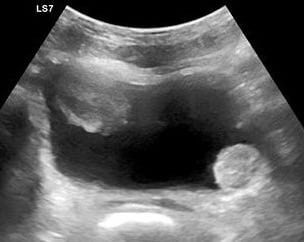

- The primary sonographic abnormality you will identify in the patient with suspected renal colic is hydronephrosis. The degree of hydronephrosis relates to the degree and extent of obstruction: (Illustration 2, Videos 11-17)

- After complete obstruction to flow, there is an acute rise in intrarenal pressure. The renal pelvis and calyces dilate first. On US you will see echo-free areas distending the normal bright (echogenic) central area of the kidney.

- As obstruction continues, the renal parenchyma becomes compressed and you see thinning of the pyramids.

- Illustration 2. Overview of degrees of hydronephrosis

- Videos 11-13. Mild hydronephrosis

- Videos 14-15. Moderate hydronephrosis

- Video 16. Moderate to severe hydronephrosis

- Video 17. Severe hydronephrosis